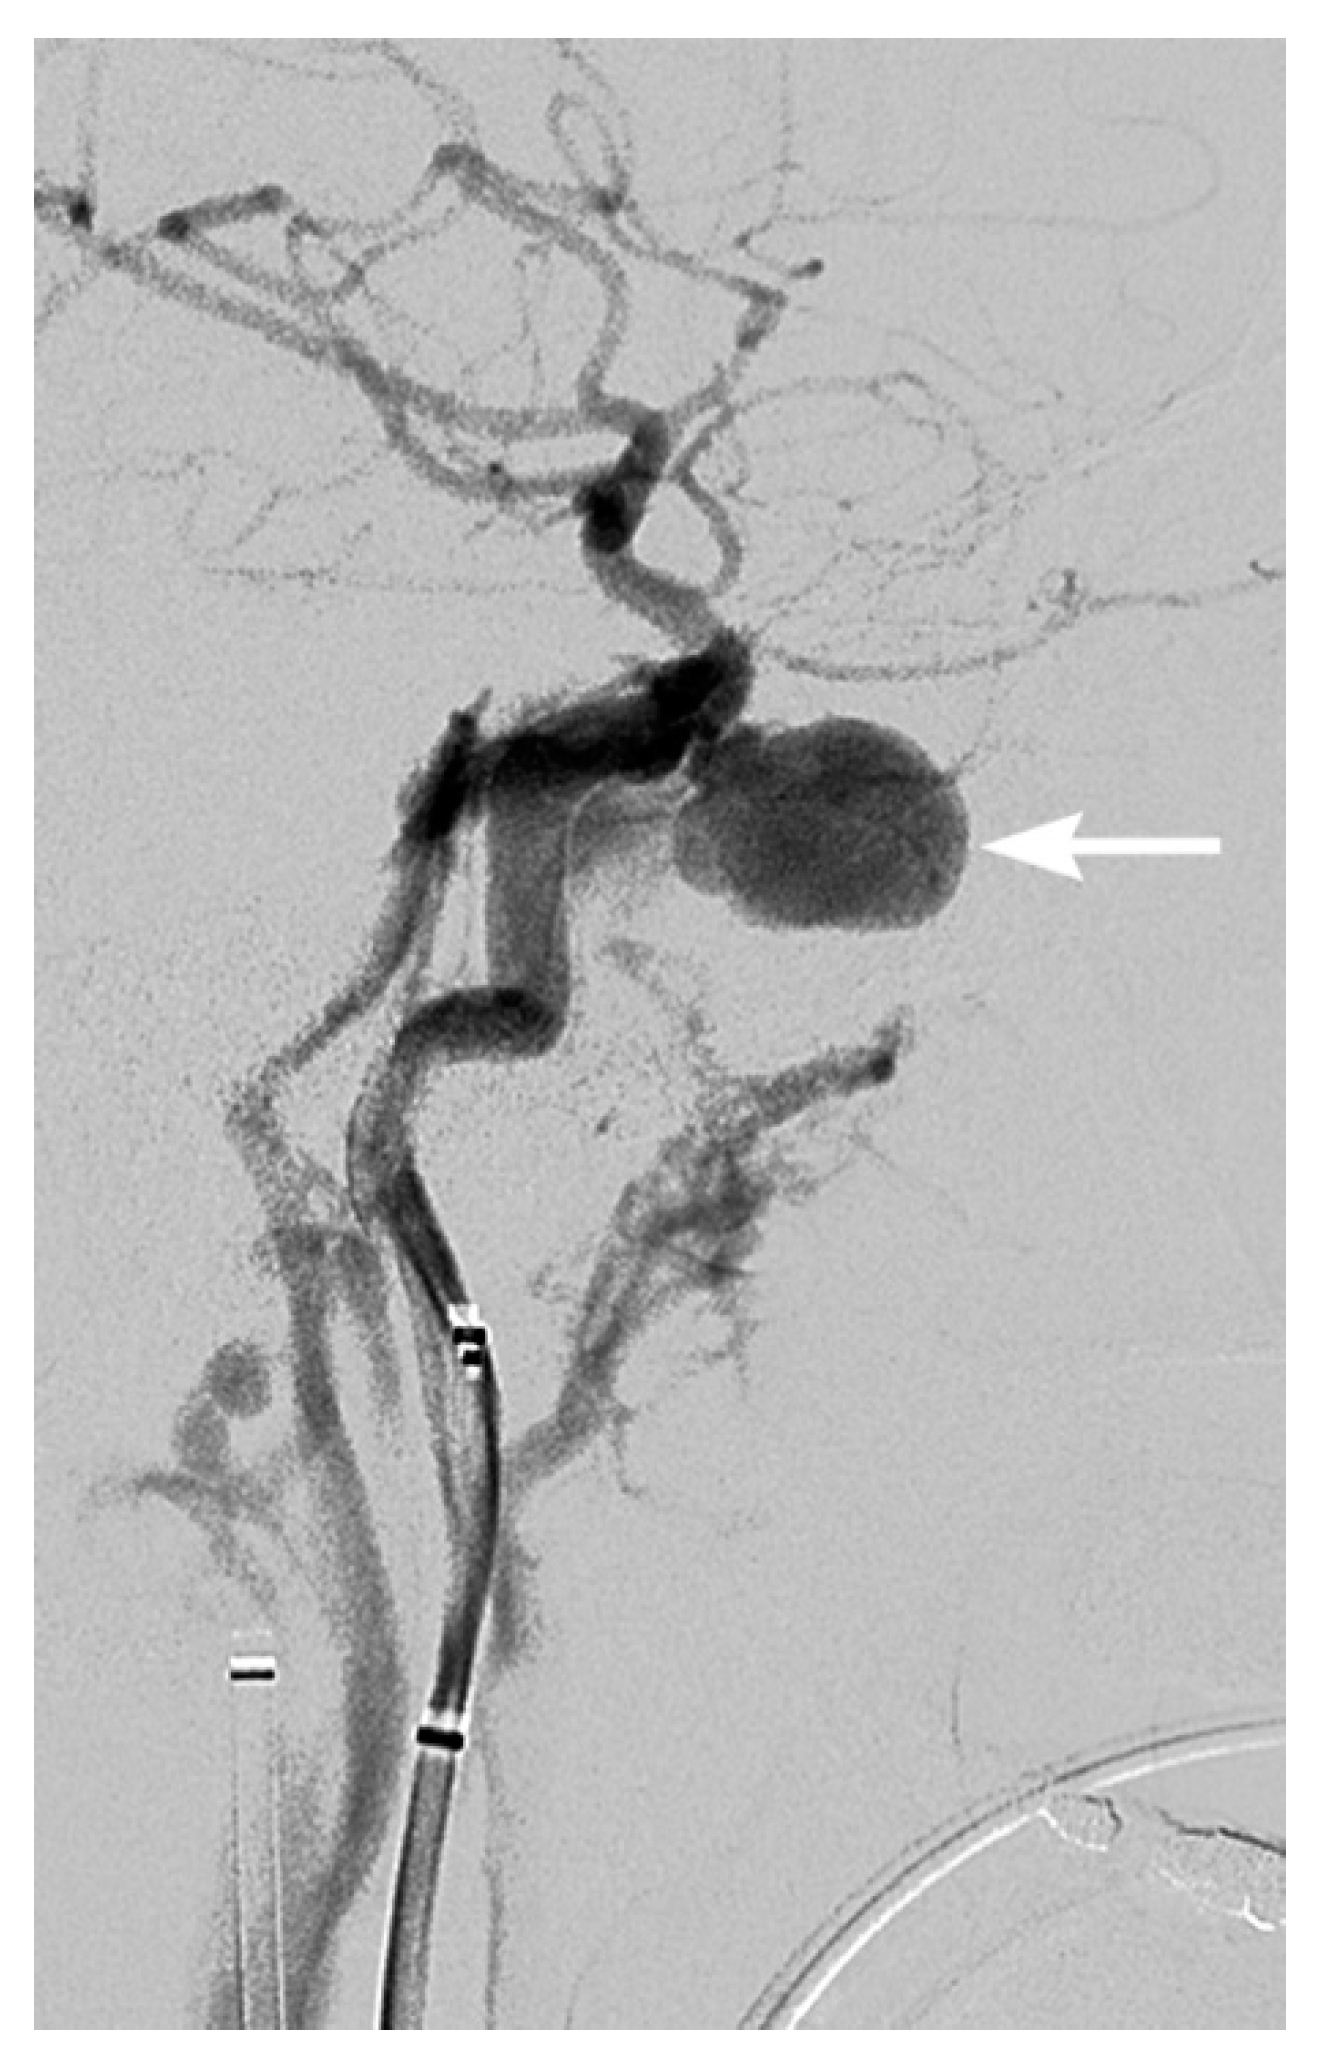

2. Imaging Techniques

3. Imaging Findings of Arterial Injury

4. Screening for Blunt Cerebrovascular Injury

5. Treatment and Follow-Up